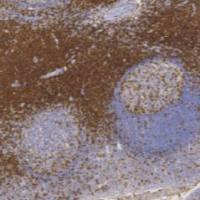

Anti-Swine IgG(H+L) mouse monoclonal antibody

| Product Name | Anti-Swine IgG(H+L) mouse monoclonal antibody |

| Cat.# | TD-AB0099 |

| Package | 25 μl/100 μl/200 μl |

| Applications | WB |

| Immunogen | Swine |

| Reactivity | Swine IgG(H+L) |

| Host species | Mouse |

| Ig class | IgG1 |

| Purity | Protein A/G Affinity Purification |

| Immunoglobulin G (IgG) is one of the most abundant proteins in serum with normal levels between 9.5-12.5 mg/ml in adult blood. IgG is important for our defense against microorganisms and the molecules are produced by B lymphocytes as a part of our adaptive immune response. The IgG molecule has two separate functions; to bind to the pathogen that elicited the response and to recruit other cells and molecules to destroy the antigen. The variability of the IgG pool is generated by somatic recombination and the number of specificities in an individual at a given time point is estimated to be 1011 variants. | |